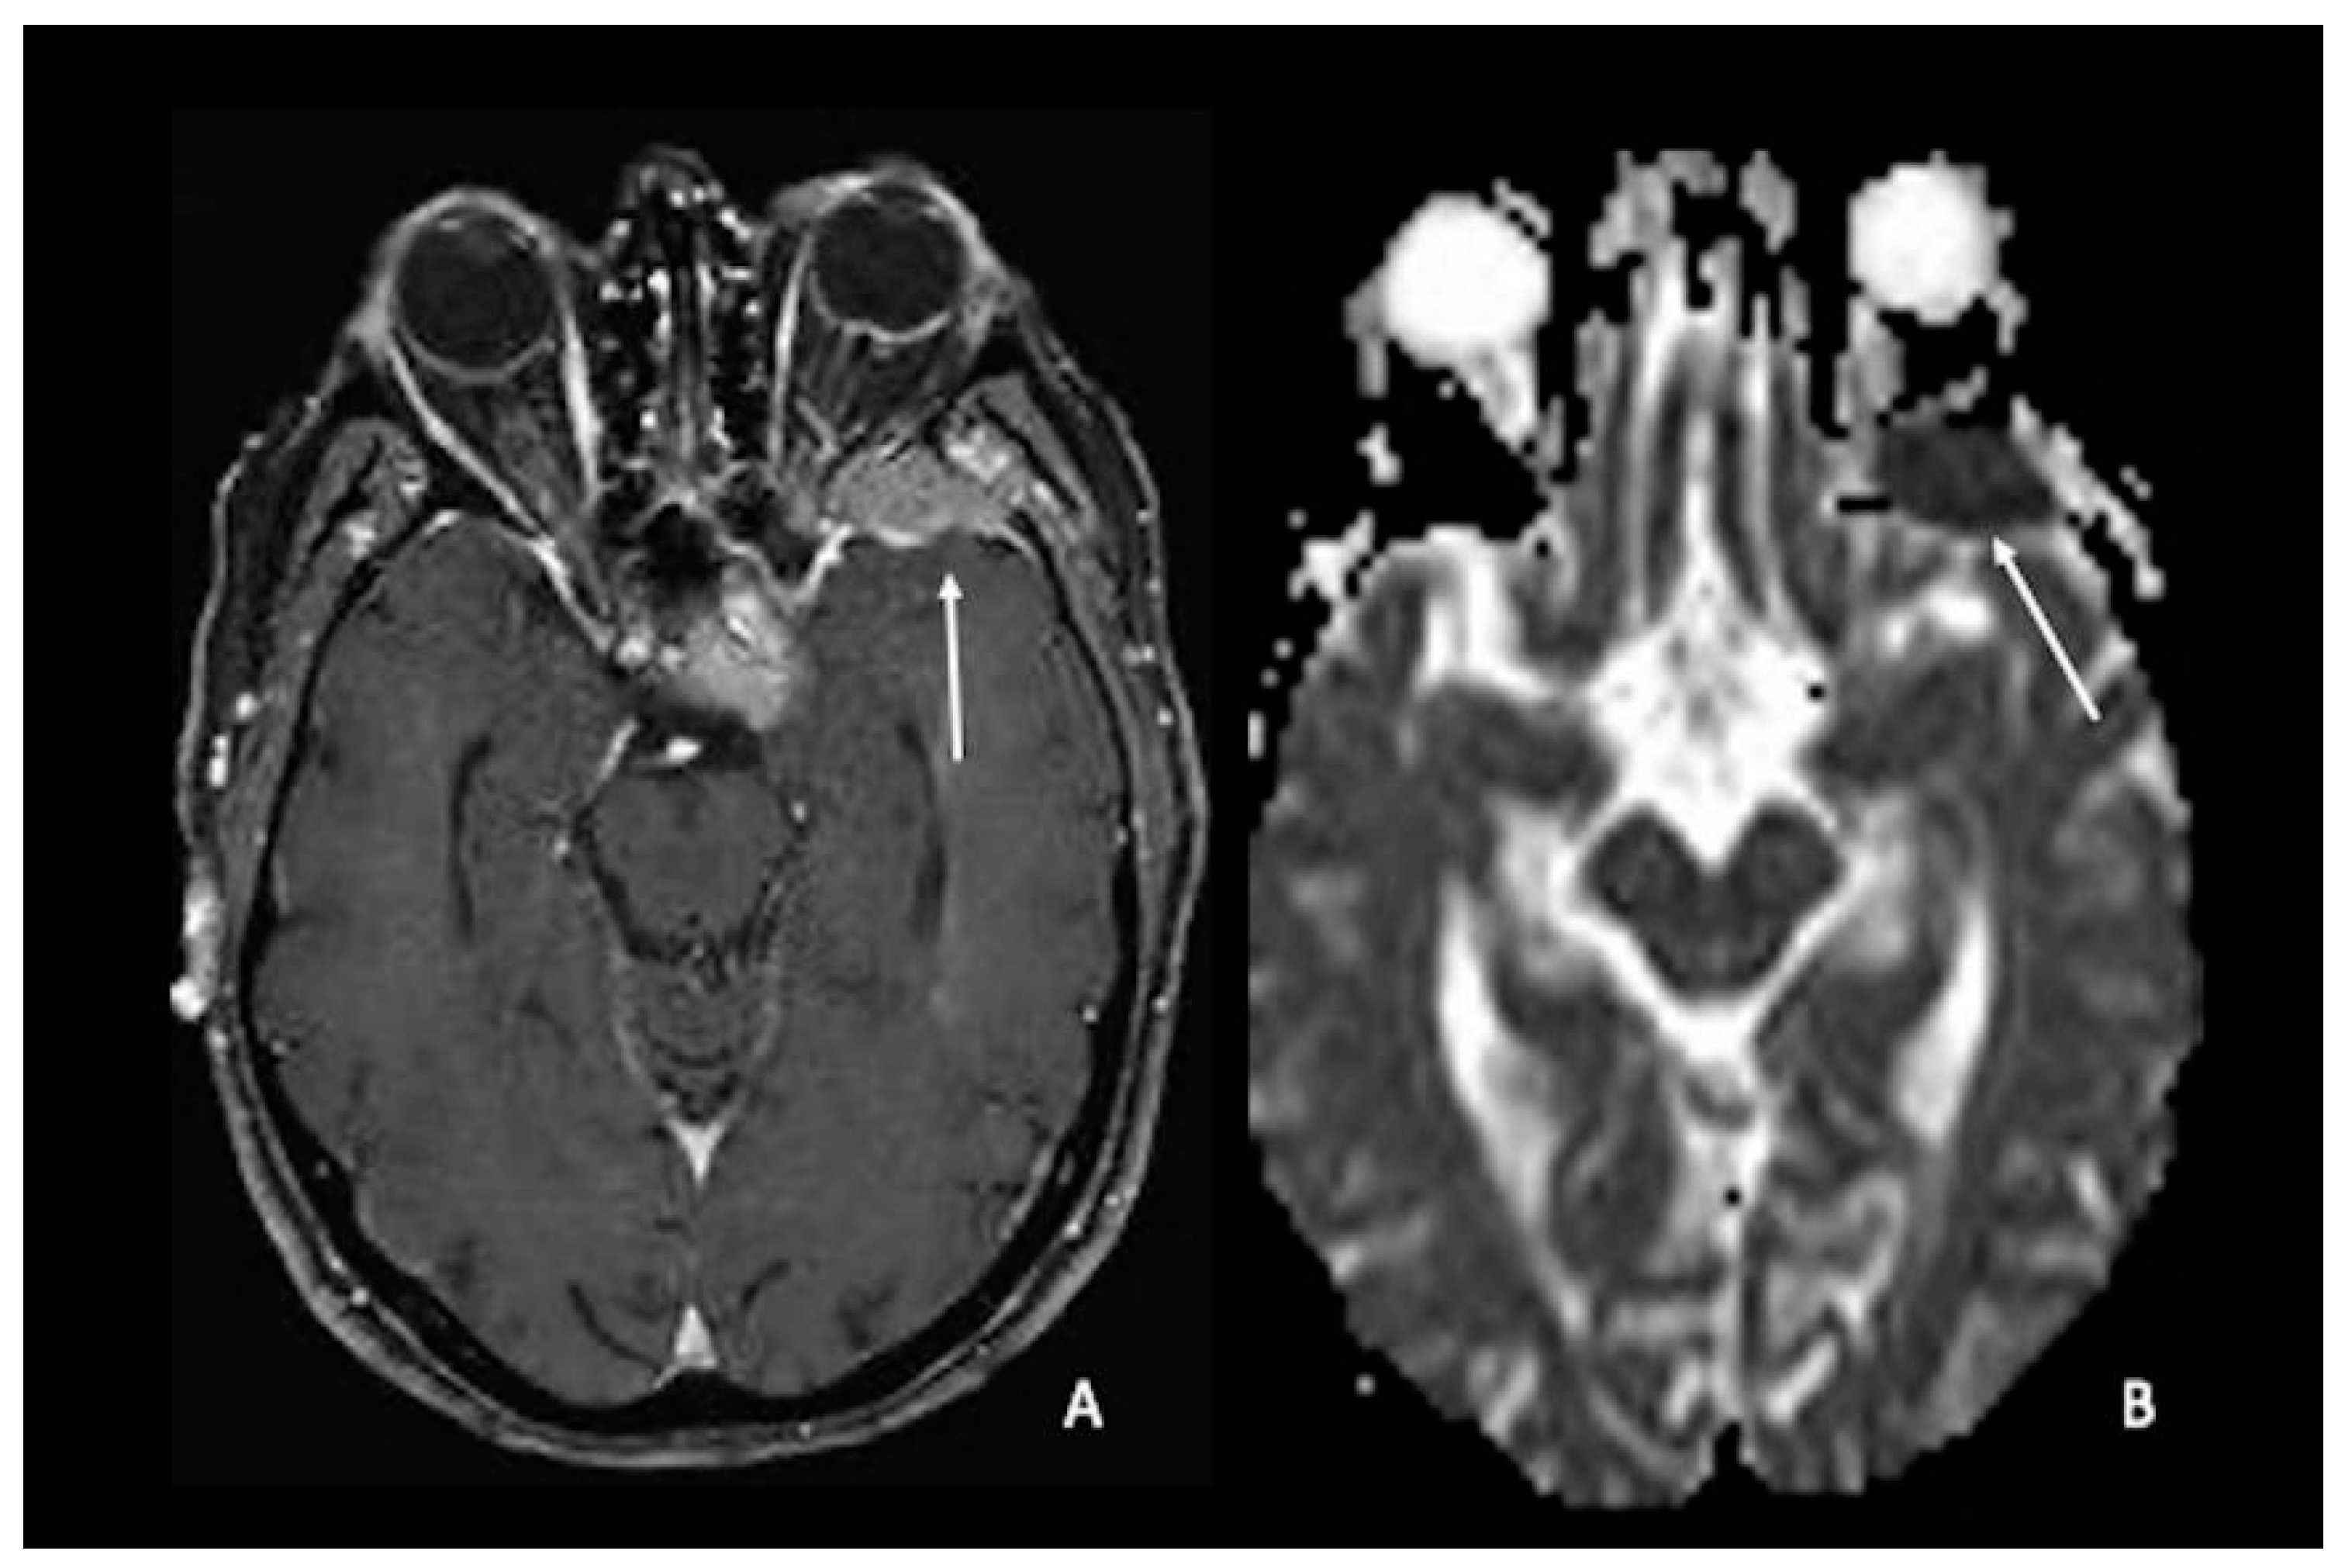

7. Metastasis

- Barajas, R.F., Jr.; Cha, S. Metastasis in Adult Brain Tumors. Neuroimaging Clin. N. Am. 2016, 26, 601–620. [Google Scholar] [CrossRef]

- Duygulu, G.; Ovali, G.Y.; Calli, C.; Kitis, O.; Yünten, N.; Akalin, T.; Islekel, S. Intracerebral metastasis showing restricted diffusion: Correlation with histopathologic findings. Eur. J. Radiol. 2010, 74, 117–120. [Google Scholar] [CrossRef] [PubMed]

- Hayashida, Y.; Hirai, T.; Morishita, S.; Kitajima, M.; Murakami, R.; Korogi, Y.; Makino, K.; Nakamura, H.; Ikushima, I.; Yamura, M.; et al. Diffusion-weighted imaging of metastatic brain tumors: Comparison with histologic type and tumor cellularity. AJNR Am. J. Neuroradiol. 2006, 27, 1419–1425. [Google Scholar] [PubMed]

- Meyer, H.J.; Fiedler, E.; Kornhuber, M.; Spielmann, R.P.; Surov, A. Comparison of diffusion-weighted imaging findings in brain metastases of different origin. Clin. Imaging 2015, 39, 965–969. [Google Scholar] [CrossRef]